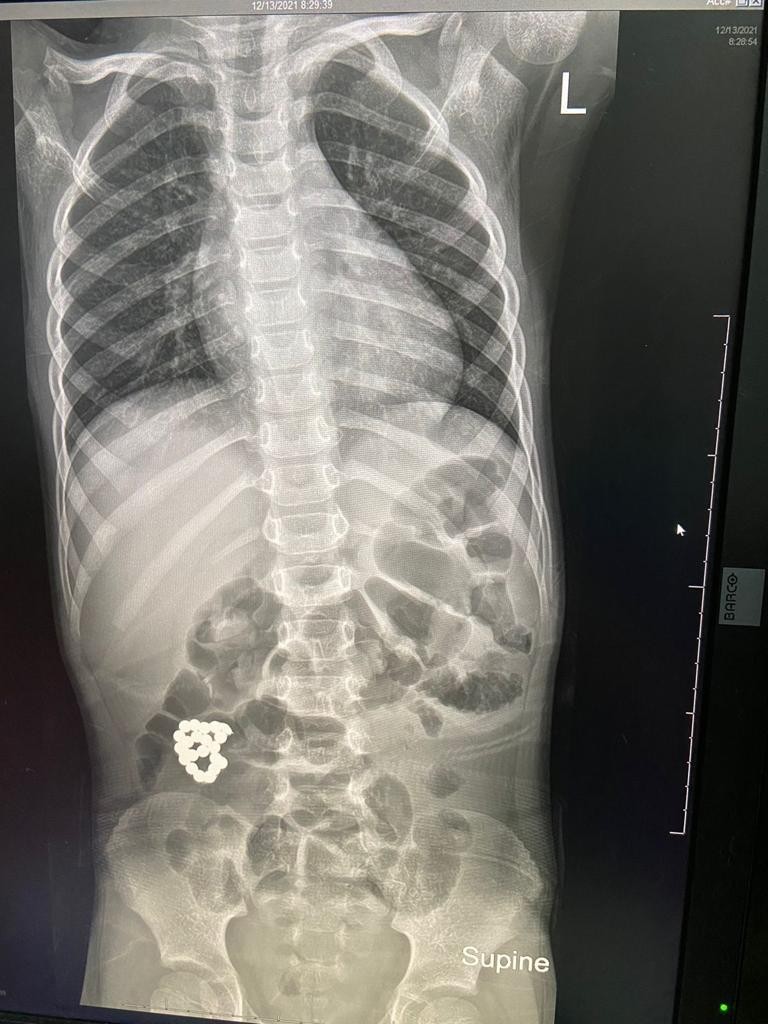

تمكن فريق طبي بمستشفى الملك عبد العزيز بجدة بقيادة بروفيسور جراحة الأطفال الدكتور عمر منصور من إنقاذ حياة طفل في السادسة من عمره، حضر لطوارئ المستشفى يشتكي من ألم في البطن ملازمه منذ ٤ أيام وازدادت الآلام مع الوقت، حيث تم عمل الفحوصات اللازمة، وأظهرت صور الأشعة وجود جسم غريب في الأمعاء.

وعلى الفور تم إدخال الطفل لغرفة العمليات واستخراج الجسم الغريب، كما تضرر جدار الأمعاء، حيث تم استئصال الأجزاء المتضررة في عملية أستغرقت ساعتين ونصف تكللت بالنجاح ولله الحمد والطفل في حالة مستقرة بفضل الله، في قسم التنويم العادي وحالته في تحسن.